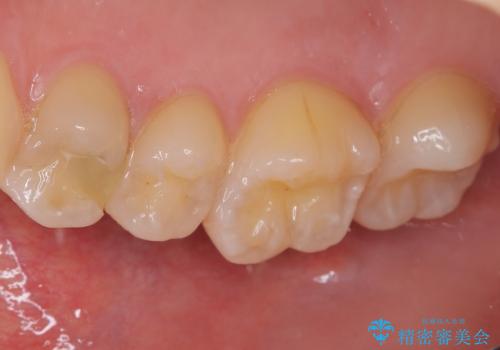

フロスの引っ掛かりやレントゲン像から、CRを除去し、虫歯を徹底的に除去し、精度の高いセラミックインレーにて修復することとしました。

レントゲン像から、隙間のない精度の高い詰め物が入っていることが確認できます。